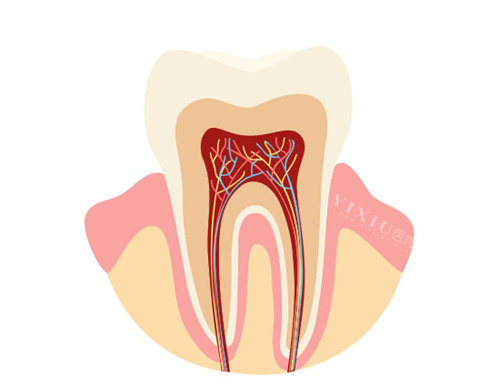

当龋洞已经形成,修复治疗成为必要手段。医生会根据龋洞大小和位置选择玻璃材料水门汀或复合树脂等材料进行充填,修养牙齿形态和功能。如果龋坏已侵犯牙髓,出现牙髓炎症状,则需进行牙髓治疗,包括牙髓切断术和根管治疗术,通过去除感染牙髓组织来消除炎症,保存患牙。对于严峻龋坏无法保留的乳牙,医生会建议及时拔除,以免影响恒牙的正常萌出和排列。